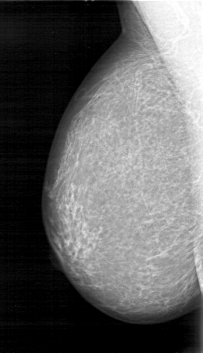

D_4026_1.RIGHT_CC

RIGHT_CC LINES 5206 PIXELS_PER_LINE 2911 BITS_PER_PIXEL 12 RESOLUTION 43.5 NON_OVERLAY